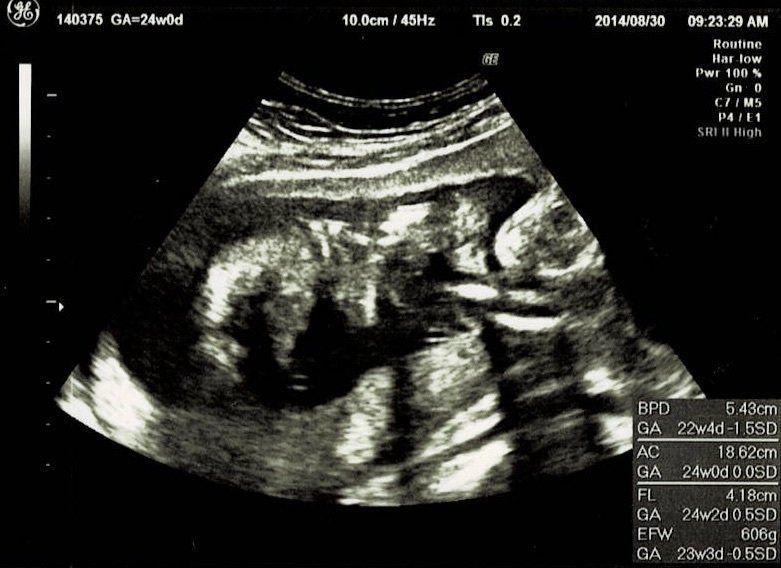

妊娠24週目エコー写真 お顔がなかなか見られない 夏の妊娠はとにかく暑い

夏真っ盛り。妊娠前の半袖ワンピースでどうにか乗り切っていましたが、腹帯なんて暑いものは耐えられず取ってしまいました。妊娠16周目と同じく、BPD、AC、FLを測ってもらいました。赤ちゃんのおおよその体重は606g。3Dエコーでお顔をきちんと見てみようとしますが、やはり手で隠してしまうため、なかなか見られませんでした。これでも顔が写っている一番いい3Dエコー写真です。

この日は、BPD(頭の左右幅)、AC(おなかの周りの長さ)、FL(太ももの骨の長さ)を測って、赤ちゃんの育ちぐあいを見てくれました。このエコーは足の骨を測っているところです。足の指らしき骨も見えます。先生がスムーズに赤ちゃんの頭やおなか、足を探すのが面白く、測っている最中のエコーもずっと眺めていました。